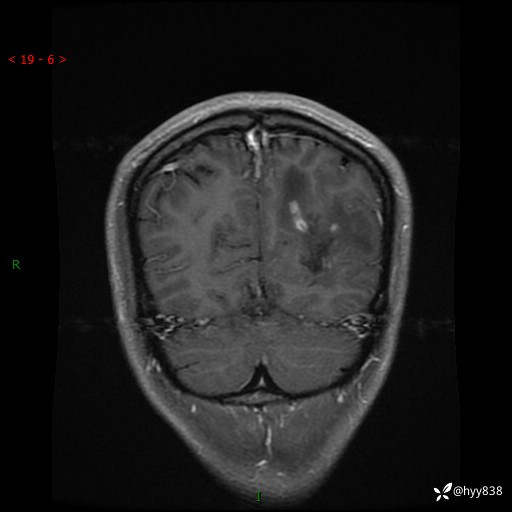

年轻女孩,间断头昏7月,乏力、嗜睡1周。难得的好病例,如何分析---(有结果)

年龄:24岁

主诉:间断头昏7月,乏力、嗜睡1周

现病史:患者5年前无明显诱因出现间断头昏,无恶心呕吐,头晕、头痛、黑矇,无抽搐、意识障碍、大小便失禁、吞咽障碍及发热等伴随症状,于当地市第一人民医院就诊,具体诊疗经过及治疗不详,1周前患者开始出现头昏,无视物旋转,伴乏力、嗜睡,现为求进一步诊治而来我院,门诊以“反复头昏待查?”收入院。 起病以来,患者精神、饮食、睡眠欠佳,体力体重较前无明显变化。

颅脑MRI平扫+增强